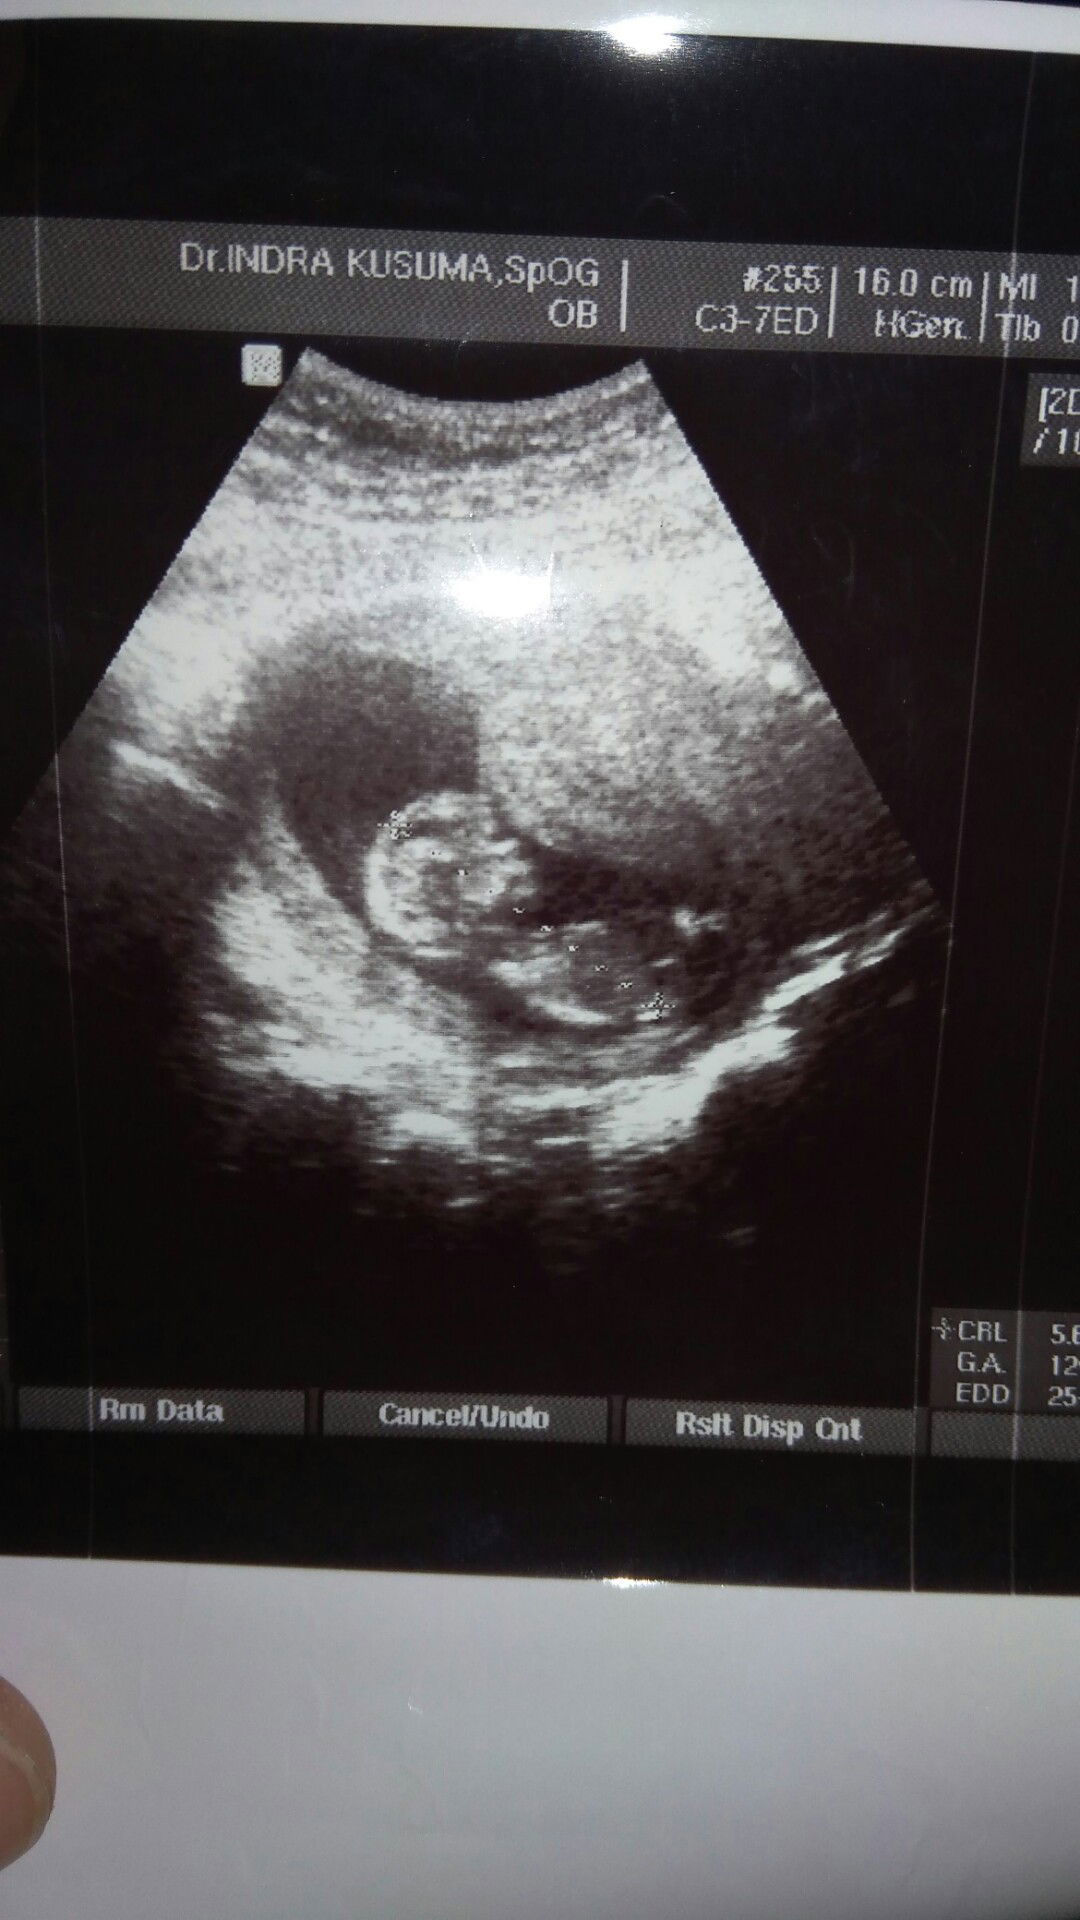

posisi bayi ada di bawah apakah normal bun?